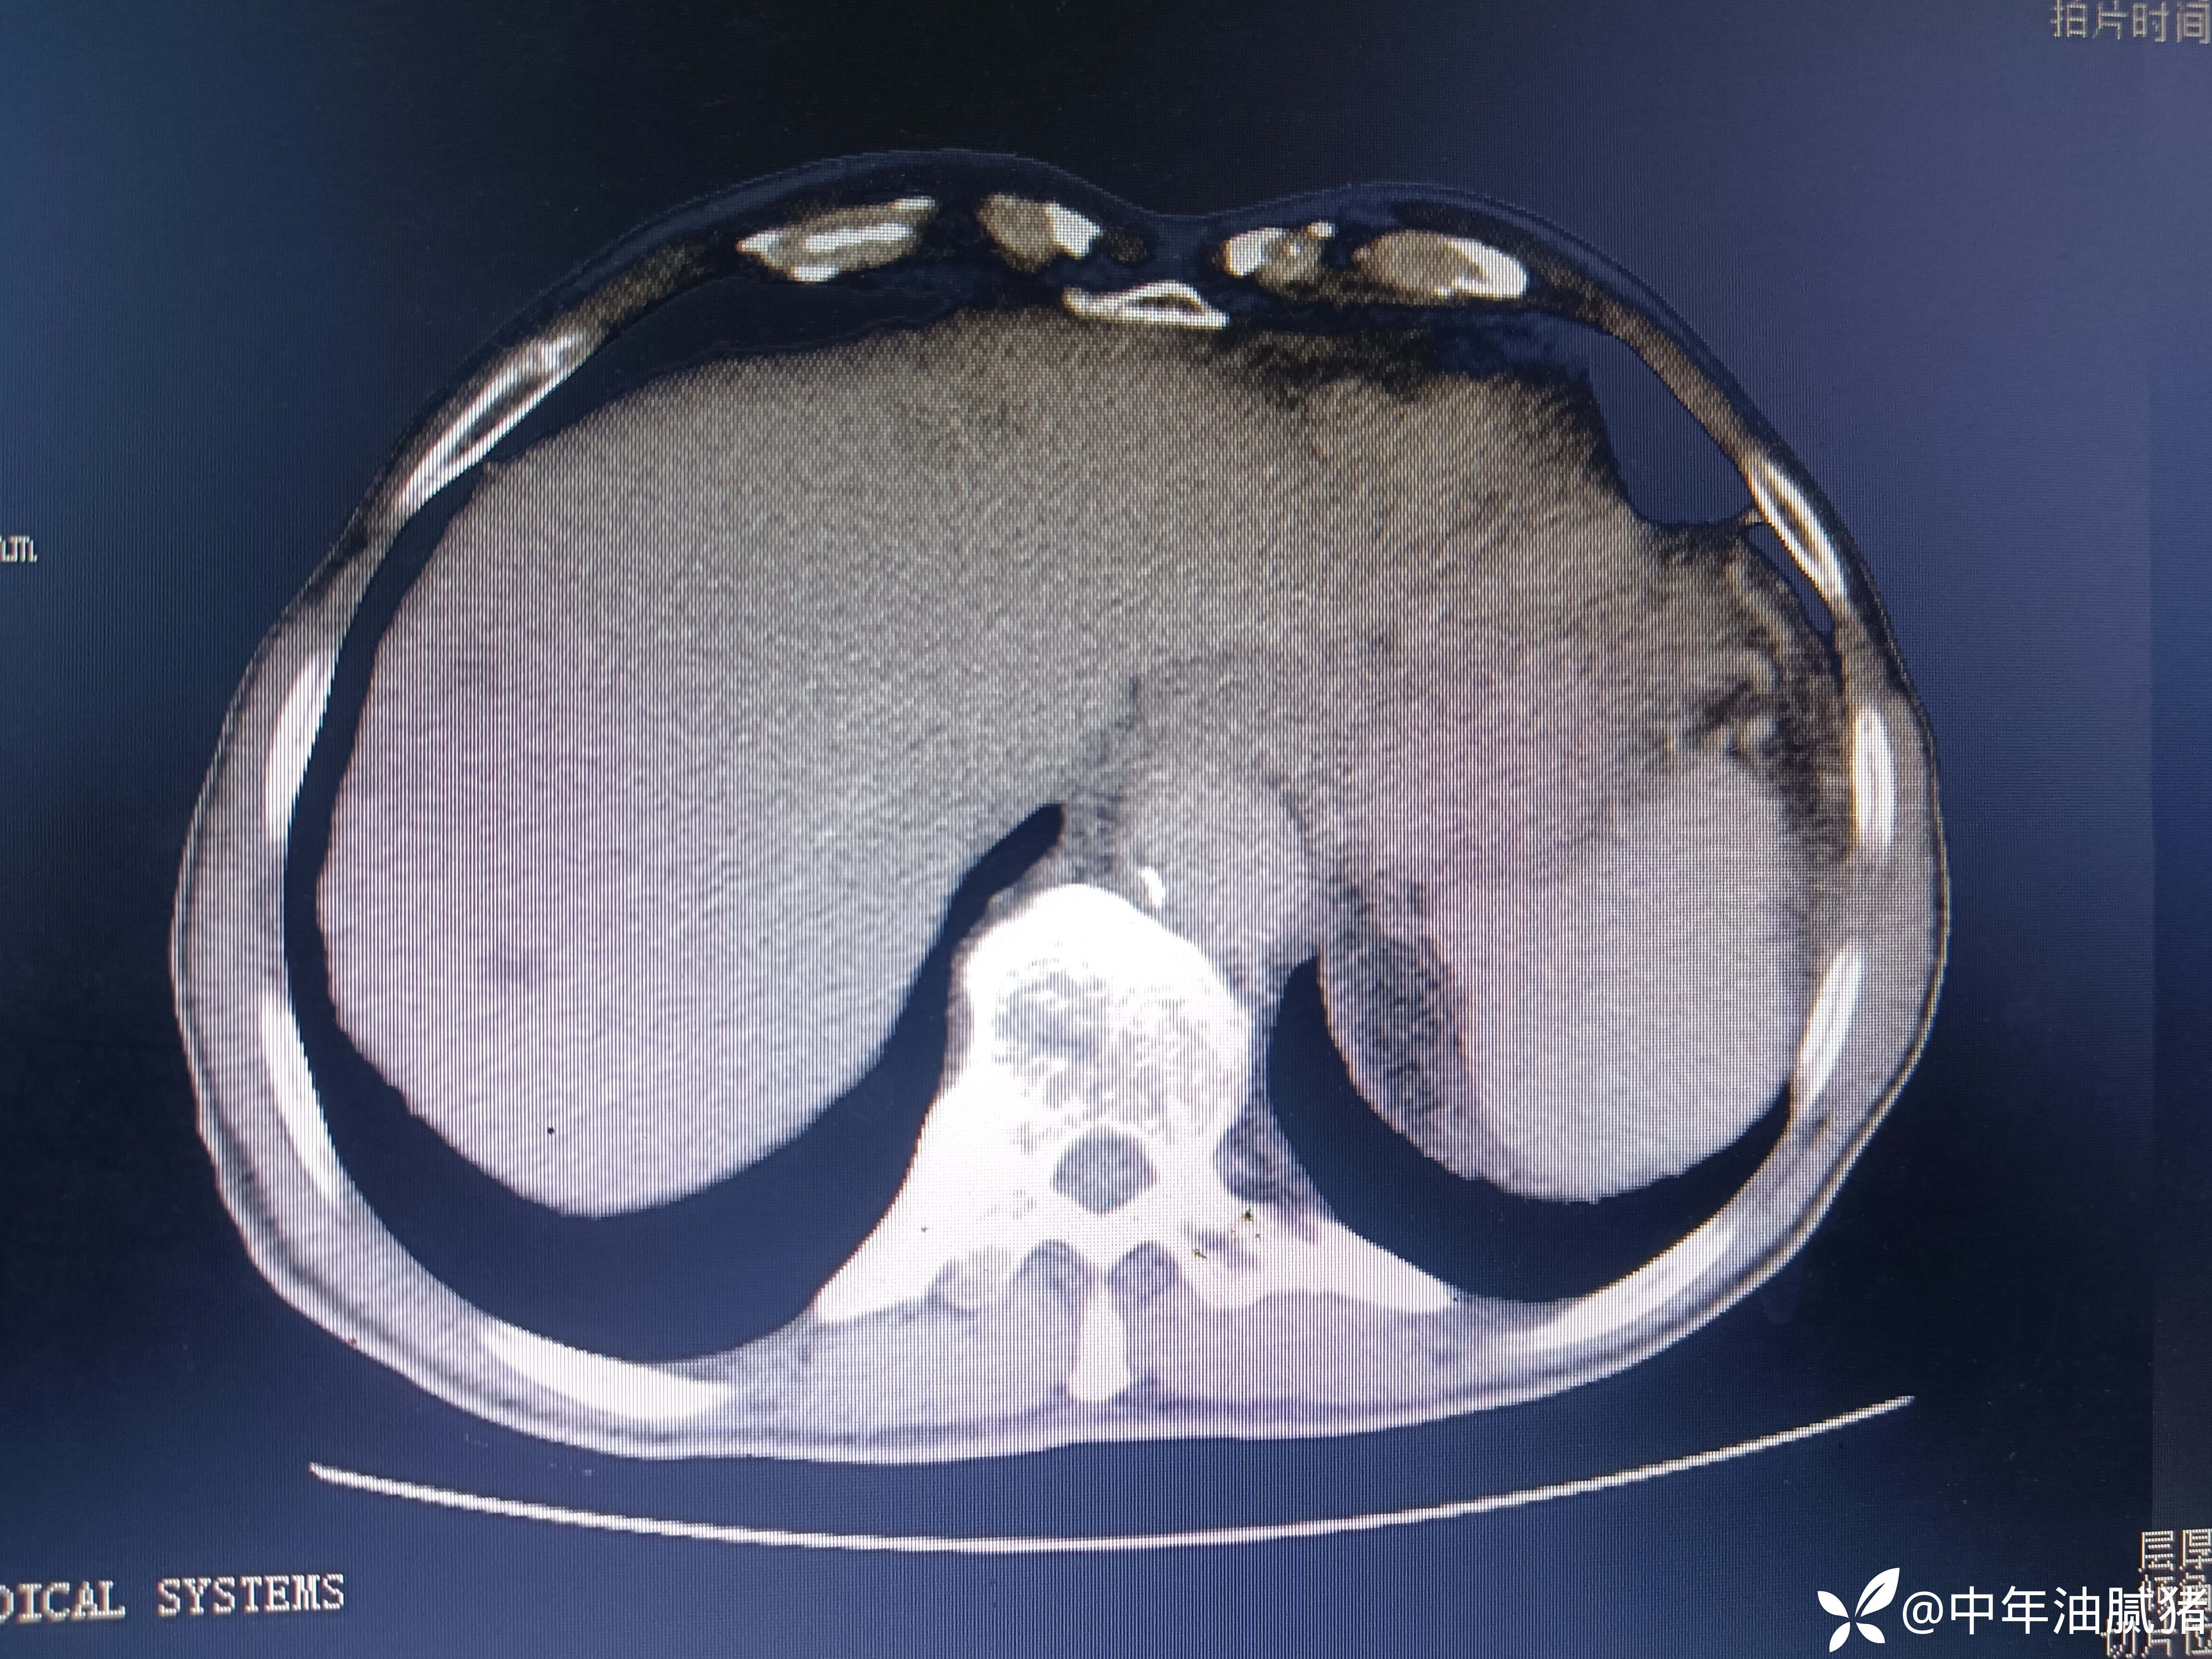

肺ct看到肝内病灶,行增强检查

建议增强ct.报告如下

考虑肝囊肿?让他走?

看后,我隐隐约约觉的不是肝囊肿那么简单?元芳,你怎么看?狄阁老,我也是这么认为!摇人,掏起手机:喂,w主任,请帮我看看这个ct。5分钟后报告修改如下